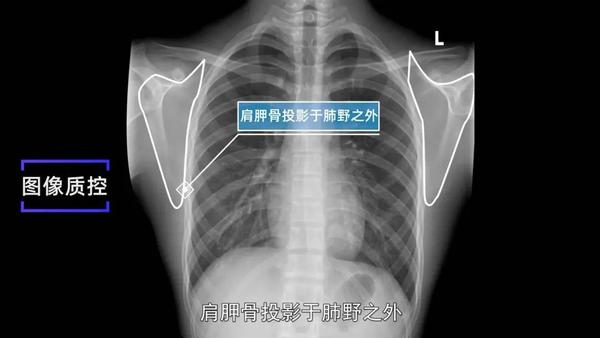

胸部x片 | 学习读片前的准备